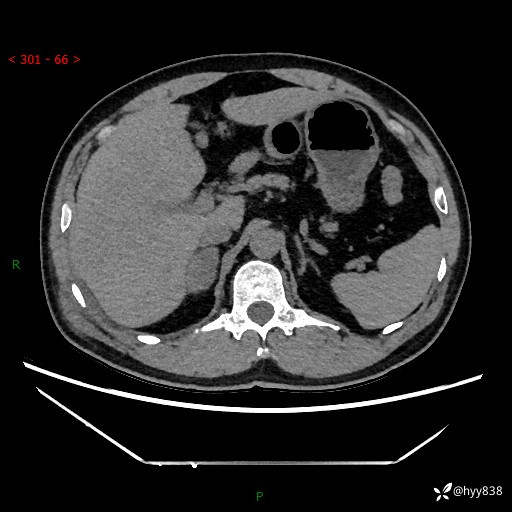

现病史:患者9月4日摔伤在深圳市宝安区中心医院行CT检查提示右侧肾上腺区结节(38*27mm),复查B超提示右侧肾上腺区可见一61*24mm异常低回声团,建议进一步检查。进一步完善增强CT后提示:右侧肾上腺区肿块及周围渗出改变,大致同前,考虑肾上腺腺瘤,不除外瘤内出血可能,否认阵发性头晕、头痛、出汗、乏力等不适,门诊以“ 右侧肾上腺肿瘤”收入住院。 起病来,患者精神、食欲、睡眠可,大便通畅,小便如上述,体力体重无明显改变。

增强(动脉期+静脉期)